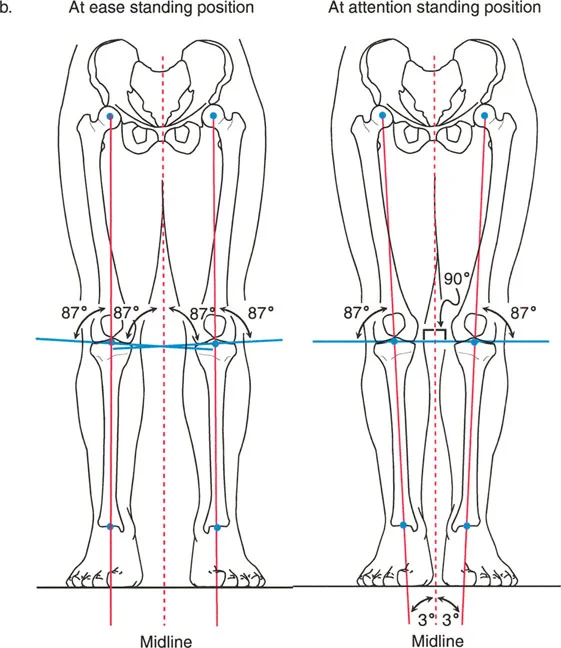

لماذا لا تكون زوايا مفصل الركبة (mLDFA و MPTA) 90 درجة تماماً؟ لماذا اختار التطور البشري أن يكون خط مفصل الركبة مائلاً بحوالي 3 درجات عن العمودي على المحور الميكانيكي؟ الإجابة تكمن في البيوميكانيكا الديناميكية للمشي على قدمين.

وضعية الوقوف "الراحة" مقابل "الاستعداد"

لفهم الميلان بمقدار 3 درجات، يجب أن ننظر إلى كيفية وقوف البشر ومشيانهم.

- الوقوف على قدمين (القدمان متباعدتان): عندما نقف والقدمان متباعدتان بعرض الحوض، تكون عظمتي الساق عموديتين على الأرض المستوية. في هذا الوضع، يكون المحور الميكانيكي عمودياً على الأرض، ويكون خط مفصل الركبة مائلاً بزاوية 3 درجات فحج (valgus) بالنسبة للخط العمودي.

- وضعية "الاستعداد" (القدمان متقاربتان): عندما نضم القدمين معاً، يصبح المحور الميكانيكي للطرف مائلاً بزاوية 3 درجات بالنسبة للخط العمودي على الأرض. في هذه الوضعية، يصبح خط مفصل الركبة موازياً تماماً للأرض.

حركية المشي

عند المشي، لا نبقي أقدامنا متباعدة بعرض الكتفين. بل نضع قدماً أمام الأخرى على طول مسار خط المنتصف. خلال مرحلة الوقوف على ساق واحدة أثناء المشي، تكون الساق التي تحمل الوزن مائلة (مقربة) إلى الخط العمودي بحوالي 3 درجات.

ولأن الزاوية الفخذية البعيدة الوحشية الميكانيكية (mLDFA) هي حوالي 87 درجة والزاوية الظنبوبية القريبة الإنسية الميكانيكية (MPTA) هي حوالي 87 درجة، فإن هذا الانحراف المدمج بمقدار 3 درجات يلغي تماماً الميلان بمقدار 3 درجات للساق أثناء المشي. وهذا يسمح لخط مفصل الركبة بالحفاظ على توجيه مثالي وموازٍ للأرض أثناء المشي. يضمن خط المفصل الموازي للأرض تقليل قوى القص وتوزيع قوى الضغط بالتساوي عبر الأجزاء الداخلية والخارجية من الركبة.